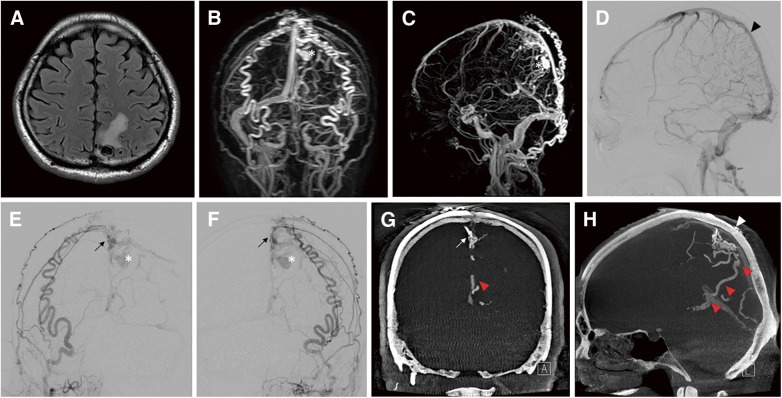

Abstract Image